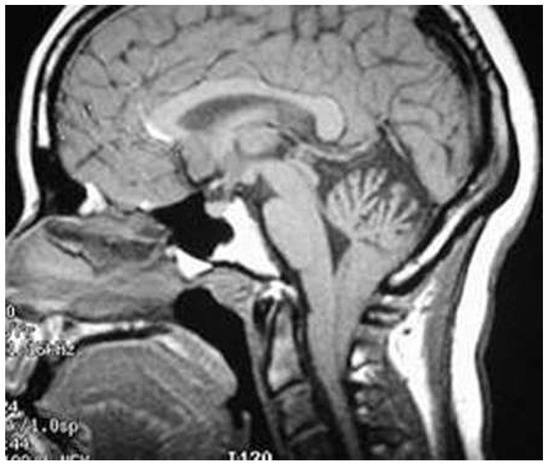

Malformation d’Arnold-Chiari et apnée centrale du sommeil

by Kokou Mensah Guinhouya, Damelan Kombate, Mofou Belo, Koffi Agnon Balogou and Kodjo Eric Grunitzky

Swiss Arch. Neurol. Psychiatry Psychother. 2015, 166(3), 99-100; https://doi.org/10.4414/sanp.2015.00320 - 1 Jan 2015

Observation Un patient de 40 ans, pesant 70 kg pour 180 cm de taille (IMC = 21,6), cadre supérieur, sans facteur de risque cardiovasculaire connu ni notion familiale de migraine, consulta en neurologie au CHU Sylvanus Olympio de Lomé, pour des céphalées inhabituelles [...] Read more.

Observation Un patient de 40 ans, pesant 70 kg pour 180 cm de taille (IMC = 21,6), cadre supérieur, sans facteur de risque cardiovasculaire connu ni notion familiale de migraine, consulta en neurologie au CHU Sylvanus Olympio de Lomé, pour des céphalées inhabituelles évoluant depuis un an [...] Full article